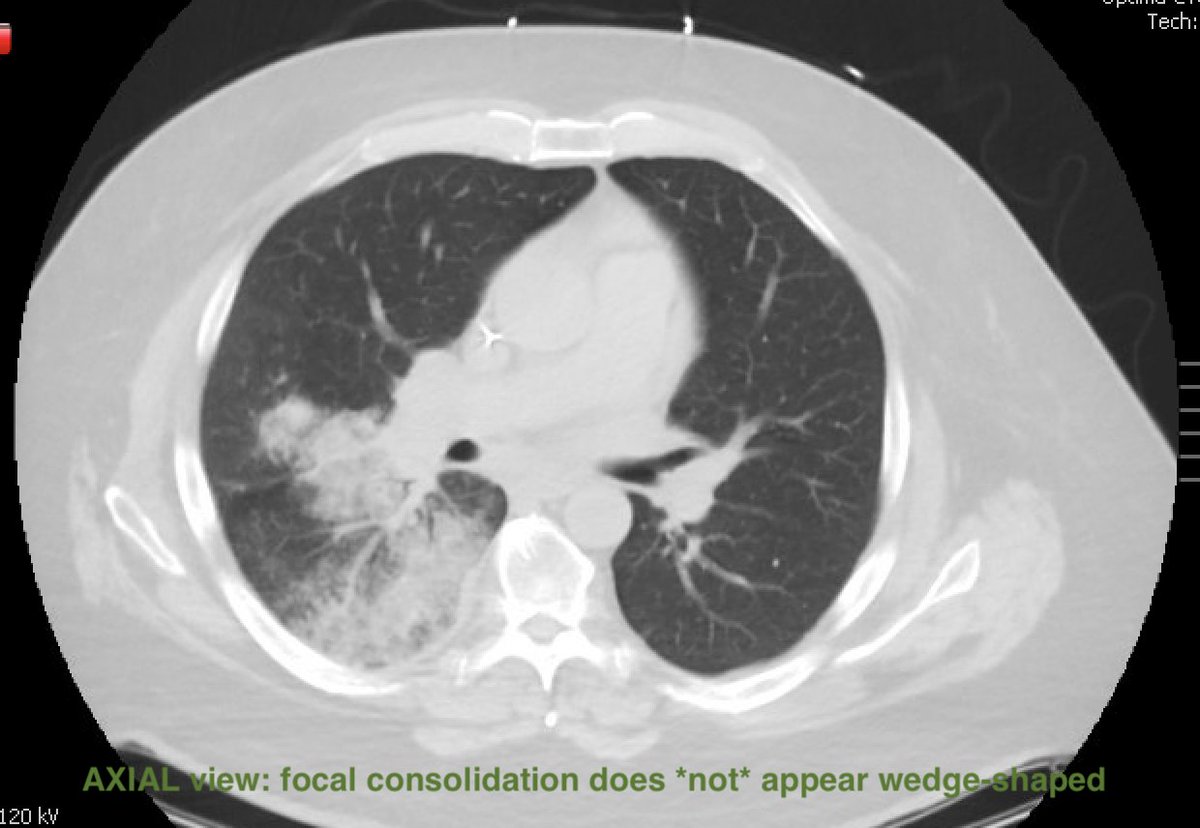

CT findings:

☠️ Wedge vs. Semicircular-shaped focal consolidation

☠️ Internal air lucencies → Cavitation ("bubbly" consolidation)

☠️ Feeding vessel